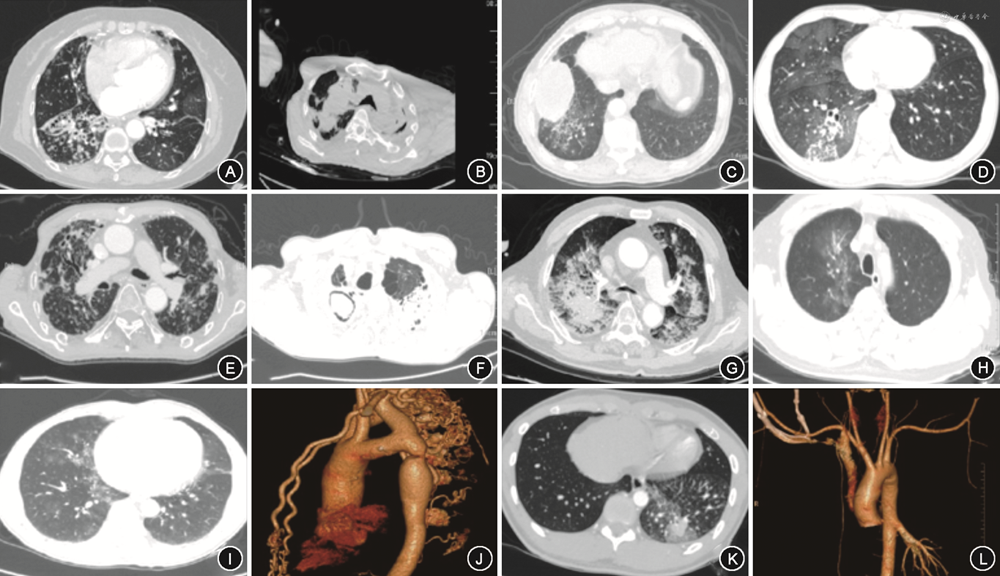

共纳入1 211例因咯血接受SAE治疗的住院患者,年龄(69±15)岁,男782例(64.6%),女429例(35.4%)。少量咯血628例(51.9%),中量咯血339例(28.0%),大量咯血244例(20.1%)。288例(23.8%)患者行肺血管介入联合呼吸内镜介入治疗,115例(9.6%)患者因大咯血窒息术前行气管插管。咯血的病因如表1所示,位于前三位的分别是支气管扩张并感染654例(54.0%),肺结核144例(11.9%),肺恶性肿瘤128例(10.6%)。咯血患者胸部CT影像学表现见图1。